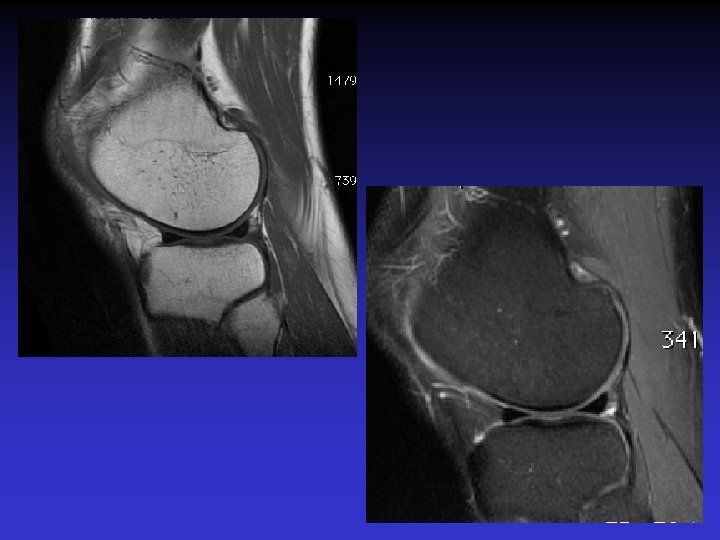

DIAGNOSTIC DIFFERENTIEL • Rupture du LCA • Tumeur synoviale

SVN